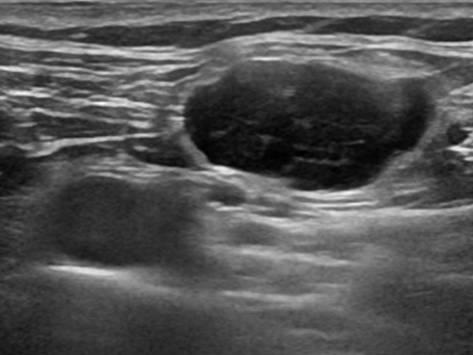

Lymphoma

» Thông tin: Nữ giới – 48 tuổi.

» Lâm sàng: Khối vùng cổ.